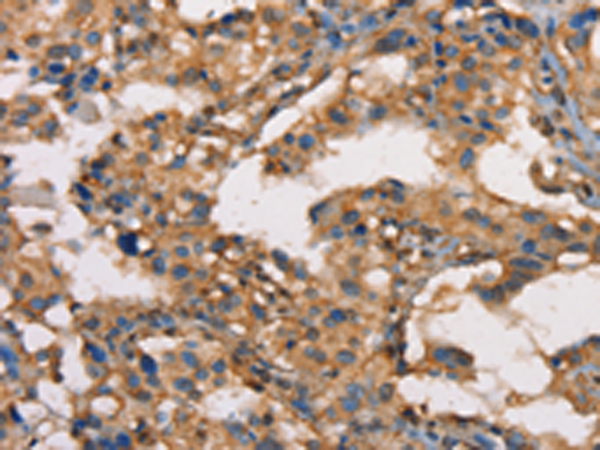

分类: 科研抗体货号: P07954别名: MAY1; PKCD; nPKC-delta应用: WB,IHC反应种属: Human, Mouse, Rat